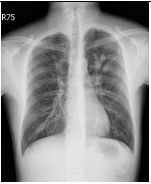

1. A 39-year-old man had this chest X-ray on his health exam. No any clinical symptoms.